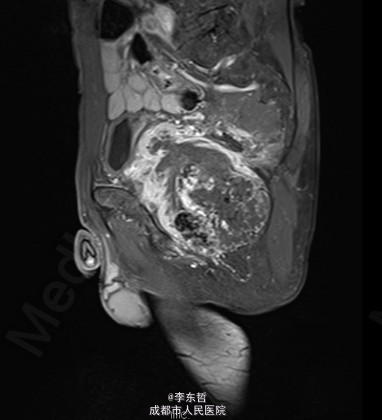

查体:臀部、会阴部、下腹部未触及包块,左下肢前内侧皮肤感觉较对侧减弱,双侧膝反射、跟腱反射正常引出,肛周皮肤感觉减退,直肠指检可触及质韧包块,活动度较差。双下肢肌力5级,双下肢各关节活动度可。 辅查:外院增强CT示:盆腔左侧壁见团块状软组织密度影,密度不均,其内见多发斑块高密度影,病灶大小约9.4*7.6cm,增强后强化不明确。我院X片示:左侧闭孔及耻骨区见不均匀高密度影,大小约6.2*6.7cm。我院MRI示:盆腔左份见长T1长T2肿块影,大小约10.3*7.7*10.5cm,向前推挤膀胱,向右推挤前列腺。我院骨扫描显示:耻骨联合及左侧耻骨支核素浓集。